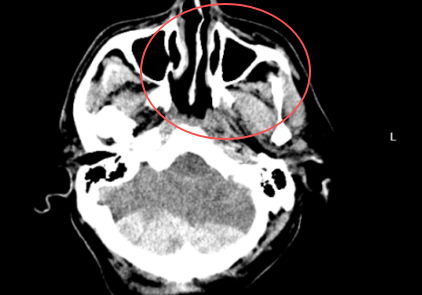

PART01危重患者緊急入院4月18日凌晨3時,一名因醉酒摔倒致頭部外傷、意識模糊的患者被緊急送至我院急診科。入院時患者頭部持續(xù)出血、右側(cè)肢體偏癱,頭顱CT檢查提示“左側(cè)額葉腦挫裂傷合并左側(cè)額顳部硬膜下血腫”,病情危重。凌晨3點急診CT神經(jīng)外科團隊迅速響應,嚴密監(jiān)測患者生命體征。然而,隨著時間推移,患者頭痛加劇,復查CT顯示顱內(nèi)血腫范圍擴大,腦組織受壓明顯,需立即手術(shù)干預。上午9點CT復查PART02血腫擴大危及生命面對緊急情況,神經(jīng)外科趙堅柱副主任醫(yī)師帶領(lǐng)團隊快速制定手術(shù)方2025-04-26